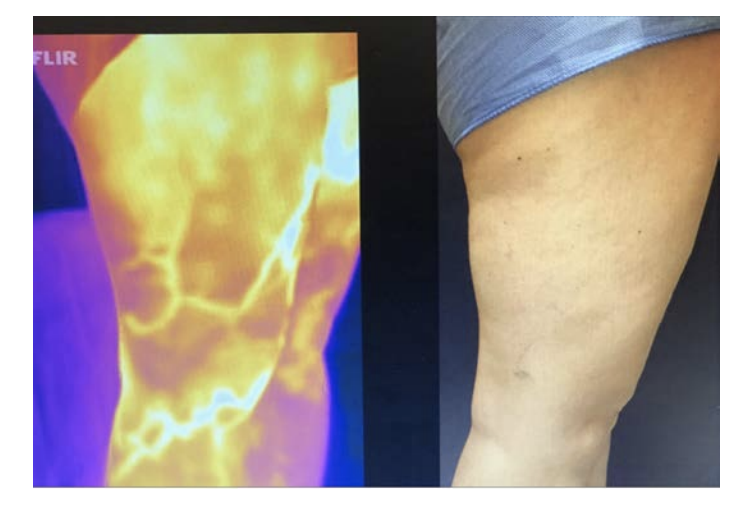

Over the decade 2010-2020, thermal imaging cameras have become more available, cheaper, smaller and more usable. In 2015 the authors started investigating the use of TI for superficial vein disease. It soon became obvious that varicose veins showed up very well on thermal imaging. Some authors have concluded that the increased heat over veins is caused by inflammation.4 We believe that we may be the first to describe that the increased heat pattern seen over the insufficient superficial veins is due instead to the core blood leaking toward the skin surface and not from inflammation. Venous blood in the deep veins has previously supplied the muscles and other structures deep to the deep fascia and is close to core body temperature (approximately 37°C). Conversely, venous blood in the normal superficial veins of the leg is blood that has been through the capillary network of the skin and subcutaneous tissue and so has equilibrated with skin temperature which is typically around 29-30°C.6 On thermal imaging normal (competent) superficial veins therefore do not show up as thermographically different from the skin and are therefore not detected. In superficial venous disease blood refluxes from the deep veins into the superficial veins and down the leg through incompetent valves, most commonly the great saphenous vein (GSV), the refluxing blood is substantially hotter than the skin and heat conducts to the surface and is detected as an area of elevated skin temperature that overlies the course of the incompetent superficial vein and is easily seen on TI (Figure 2 and 3 A&B). It has been suggested that the temperature differences are caused by inflammation of the vein, despite the fact that for simple varicose veins there are none of the markers of inflammation, redness and swelling of surrounding tissue, both of which are clearly seen in superficial thrombophebitis. Histological studies of simple varicose veins confirm this with the main finding being intimal hypertrophy and fibrosis with muscle thinning.9,10 In addition, if an individual is imaged while standing the vein pattern is very clear, 2-3 minutes after lying down the pattern is no longer present, if they stand again the vein pattern reappears. The authors believe this is clear evidence of the transient nature of the signal and its association with reflux. If it were caused by inflammation the pattern would be sustained for an extended period. The incompetent trunk vein is not usually seen as it lies deeper in its own fascial sheath. Adjacent structures to the incompetent truck vein are also at core body temperature and equally conduct heat to the surface so no excess heat is detected. Once the vein escapes the deep fascia and comes closer to the skin, the surface temperature is elevated and is typically around 33°C. This consistently creates a localised elevation in temperature along the incompetent vein of approximately 3°C when compared to nearly all adjacent anatomy, which is easily detected with modern TI cameras with sensitivity of 0.1°C.

It might be imagined that obese legs would not display vein patterns in the same way as slim individuals as the insulating effect of the thicker subcutaneous tissue was greater.4 In practice this does not seem to be the case, as the skin surface in the obese or edematous patient is likely to be cooler than that of a slim person, thus the relative temperature difference is maintained. While there has been no study of this reported in the literature the authors have not found thermal imaging of the obese leg to be any less useful (Figure 2 and 3).